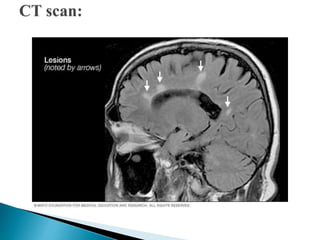

 Monitor results of X-rays, CT scans, MRIs and any lab

studies, cultures, activated partial thromboplastin time,

white blood cell count, and differentiated blood count.

Report any abnormal results to the physician.